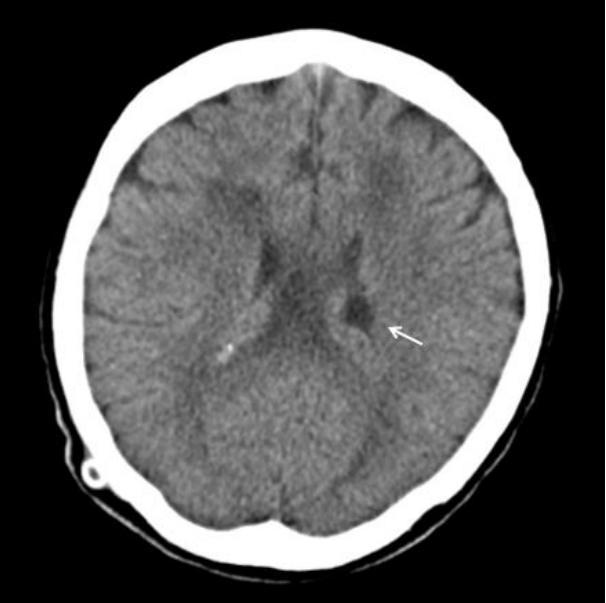

Figure 1.

Initial brain computed tomography revealing an abscess (1.7 × 1.4 cm in size, arrow) in the left periventricular area, and ventriculitis.

74세 여자가 어지럼증으로 입원하였다. 뇌척수액의 결핵균 핵산증폭 검사에서 양성 소견을 보여 결핵성 수막염으로 진단되었으며 수두증을 동반하여 뇌실복강단락술을 시행하였다. 뇌척수액과 혈액에서 결핵균 외 다른 병원균은 검출되지 않았고, Cryptococcus 항원 검사와 India ink 염색은 음성이었다. 항결핵제 치료를 시작하였고 증세 호전을 보여서 퇴원하였다.뇌실복강단락술 시행 14주 후, 환자는 열감과 구토, 의식저하를 주소로 재입원하였다. 활력 징후는 혈압 120/80 mmHg, 심박수 76회/분, 호흡수 20회/분, 체온 37.7℃였고 의식은 기면 상태였다. 혈액 검사에서 백혈구 10,400/mm3 (중성구 56.1%), 혈색소 11.4 g/dL, 헤마토크리트 33.5%, 혈소판 441,000/mm3였고, 적혈구침강속도는 75 mm/h, 고감도 C-반응단백은 5.83 mg/dL였다. Human immunodeficiency virus 항체와 신속혈장리아긴 검사, Cryptococcus 항원 검사는 음성이었다. 뇌실복강단락을 통한 뇌척수액 검사에서 압력은 120 mmH2O, 백혈구 1.8/uL, 적혈구는 검출되지 않았으며 당 62 mg/dL (혈당 139 mg/dL), 단백질 40.1 mg/dL, 아데노신디아미네이스는 3.0 IU/L였다. 뇌 컴퓨터단층촬영에서 좌측 뇌실의 조영 증가와 주위조직의 부종, 좌측 뇌실내 도관 근위부에서 1.7 × 1.4 cm 크기의 변연부에 조영증강이 되는 낭성병변이 관찰되었다(Fig. 1). 뇌실복강 단락을 통한 복강내 감염의 진행을 확인하기 위하여 복부 조영증강 컴퓨터단층촬영을 시행하여 우하복부에 위치한 도관 말단 부위에서 4.7 × 2.8 cm 크기의 조영증강되는 벽을 지닌 낭종을 확인하였다(Fig. 2). 경험적으로 ceftriaxone 2 g/day와 혐기성균에 의한 혼합 감염의 가능성을 고려하여 metronidazole 1,500 mg/day를 정맥 투여하였고 입원 병일 3일째 뇌척수액 그람 염색에서 효모균이 관찰되어 fluconazole 200 mg/day를 추가로 투여하였다. 입원 병일 7일째 복부의 낭종에 대하여 진단적 복강경 검사를 시행하였다. 복강내 도관 말단은 4 cm 크기의 투명한 액체로 채워진 낭종 안쪽에 위치하고 있었으며 주변으로 유착이 관찰되었다. 낭종과 기존의 뇌실 복강단락을 제거 후 체외 내실 배액관으로 교체하였다. 뇌척수액과 혈액 배양 검사 결과에서 2회 연속으로 Cryptococcus neoformans가 동정되어 Cryptococcus에 의한 뇌막염으로 진단하였고 배양 검사와 핵산증폭 검사에서 결핵균은 동정되지 않아 amphotericin B 0.7 mg/kg/day를 정맥 투여하고 flucytosine 100 mg/kg/day를 경구 투여하였다. 입원 병일 12일째 복부 낭종 흡인액 배양 검사에서 Pseudomonas aeruginosa와 Klebsiella species가 동정되었고 뇌실내 도관 말단 배양 검사에서 Cryptococcus neoformans가 동정되었다. Pseudomonas에 대하여 ciprofloxacin 400 mg/day를 정맥 투여하였다. 입원 병일 19일째 시행한 뇌 컴퓨터단층촬영에서 뇌농양의 크기는 1.2 × 1.0 cm로 감소하였고 수두증은 호전 소견을 보였다(Fig. 3). 입원 병일 21일째부터는 열과 신경학적 증상이 호전되고 의식상태가 명료하여 amphotericin B와 flucytosine을 중단하고 fluconazole 200 mg/day로 교체하였다. 입원 병일 30일째 연속 3번의 뇌척수액 배양 검사에서 음성 소견을 보여서 체외 내실 배액관을 제거하고 새로운 뇌실 복강 단락 도관을 배치하였으며 경구 fluconazole 200 mg/day를 6개월 이상 투약 유지하기로 하고 퇴원하였다. 6개월간의 추적 관찰 기간 동안 환자는 특별한 증세나 재발의 소견 없이 지내는 중이다.